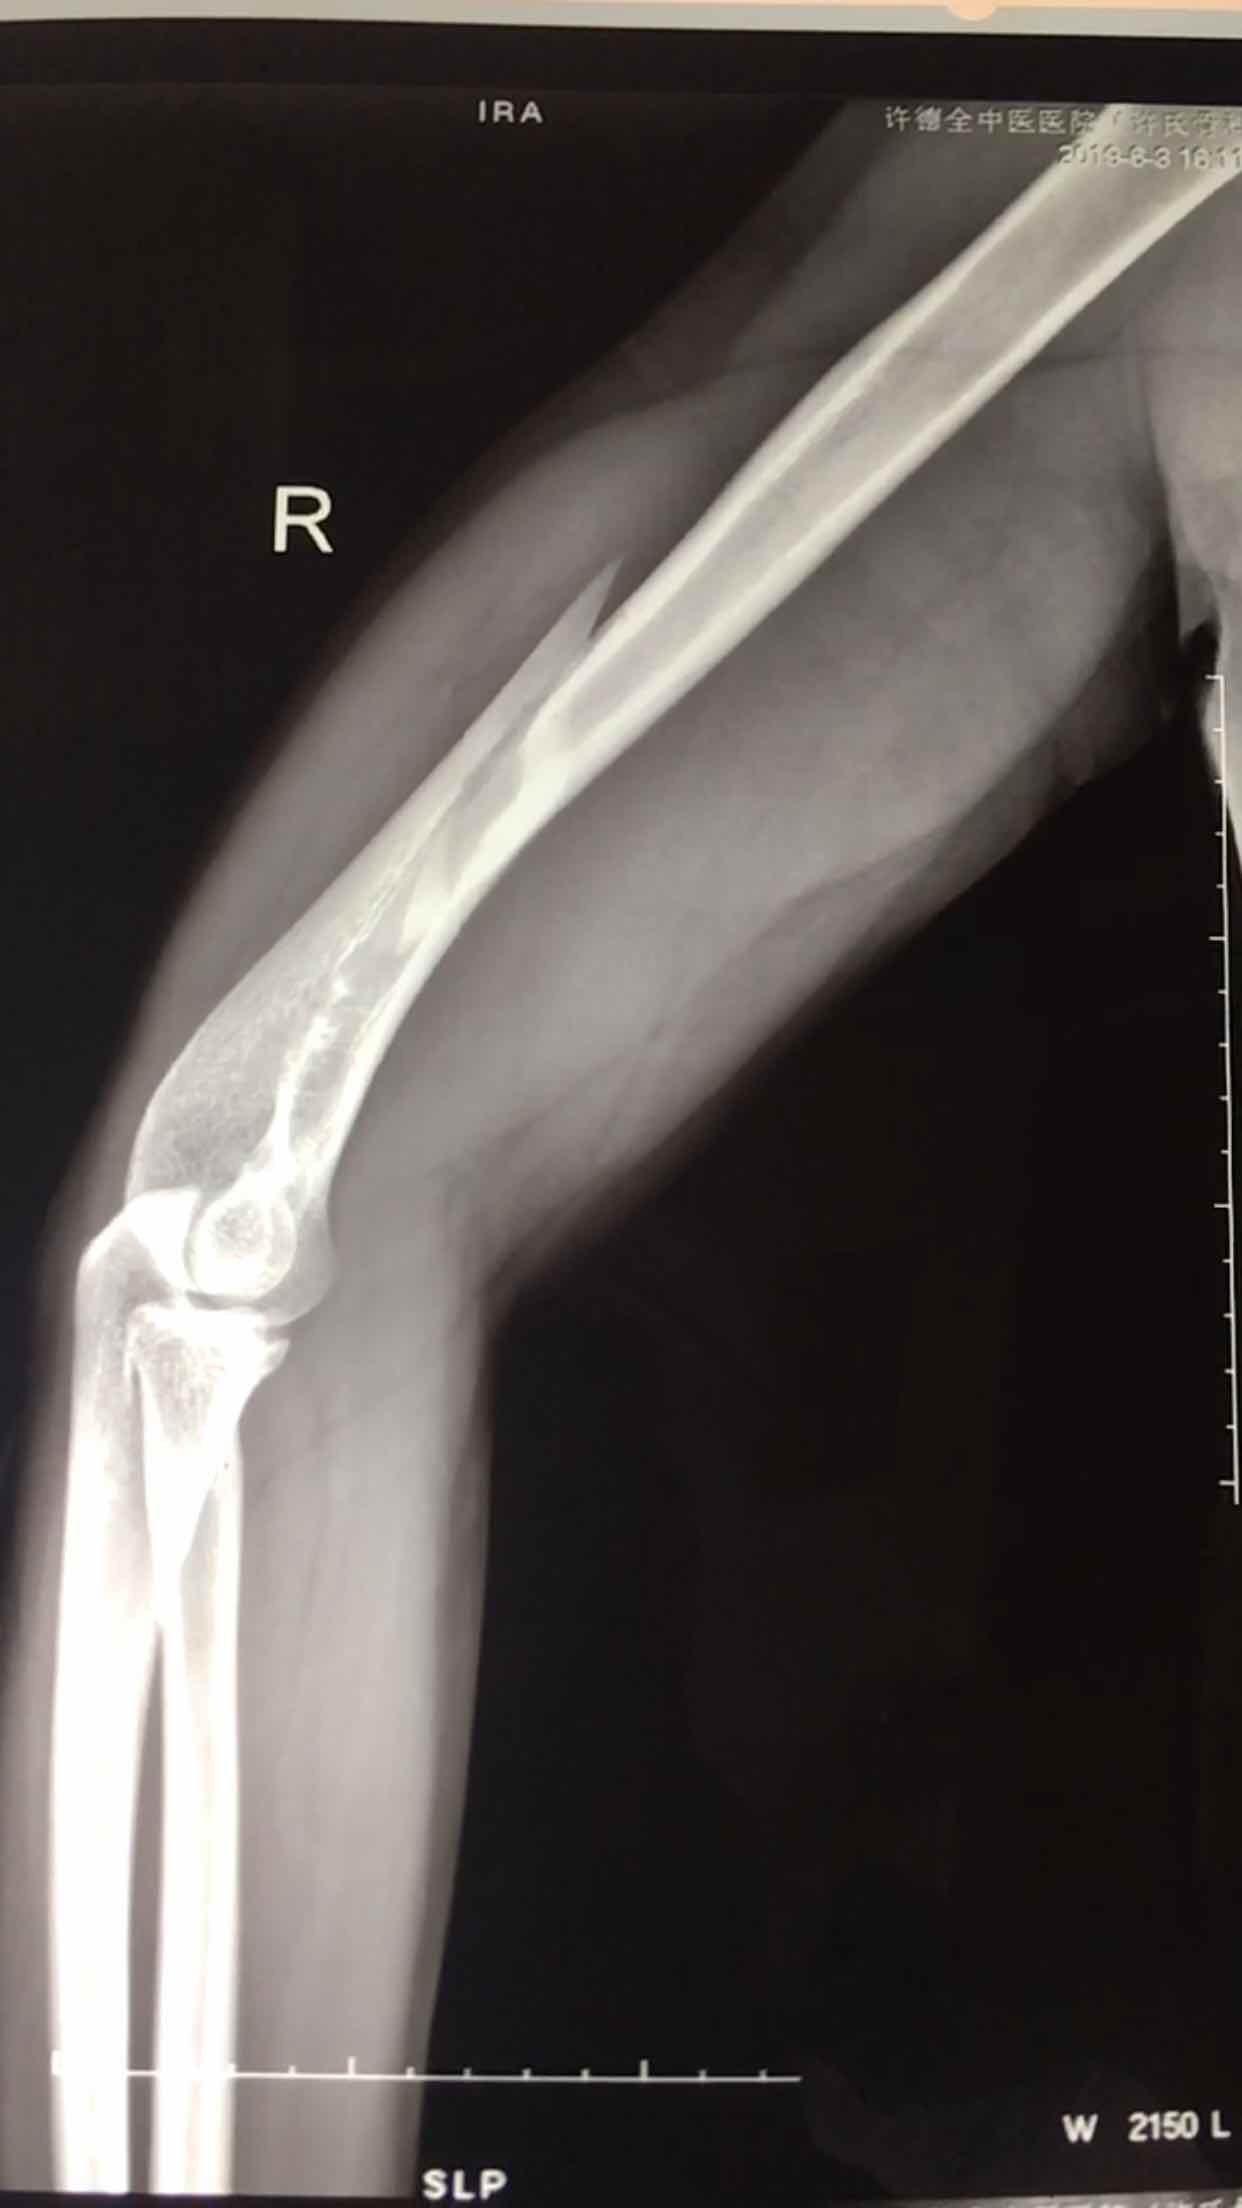

肱骨远端骨折(切复双钛板内固定)

摔伤后右肘部肿胀,畸形,活动受限2小时入院。既往身体健康,无特殊不良嗜好。从事健身教练工作数年。

生命体征平稳,心肺复未见异常。右上臂肿胀明显,畸形,局部皮色发红,皮温高,压痛及纵叩痛阳性,可及骨檫音及骨檫感,异常活动,末梢血运感觉正常。

诊断肱骨远端骨折在臂丛麻醉下行切复内固定术,术后抗炎,消肿等处理。